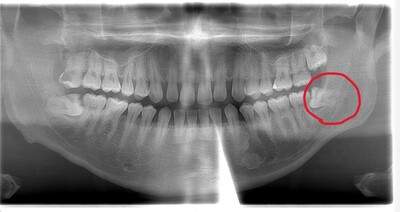

左下の歯茎が腫れている親知らずの症例

- 抜歯前写真(レントゲン、CT等)

左下の親知らず周囲歯肉が腫れていました。

また、手前の歯との間で虫歯もできていました。

| 抜歯内容 | 下顎の親知らずの抜歯希望の患者様です。 智歯周囲炎となっており、初診時では麻酔が効きづらい旨をお話しし、初診時は抗生物質をお出ししました。1週間後、ある程度歯肉の炎症がとれたことを確認して抜歯を行いました。 麻酔を行い、遠心(親知らずの奥側)歯肉と、手前の歯の頬側の歯肉を切開しました。 歯茎を開いて、手前の歯と引っかかっている部分をカットしました。 その後、骨からでている歯冠部(頭の部分)をカットしました。 その後へーベルで歯根(骨に埋まっている部分)を脱臼し、抜歯を終えました。 切開した歯茎を3針縫って、治療終了となりました。 歯茎を切ったため、3日ほど腫れぼったい感じがあったようですが、痛みはほとんどなく、治癒に向かいました。 |